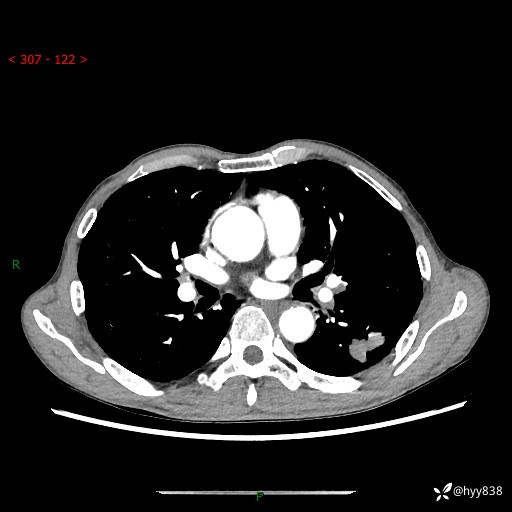

现病史:患者于1月余前无明显诱因出现背部疼痛不适,无明显咳嗽、咳痰、胸闷、咯血、发热等不适,后于2024.5.3至当地市人民医院行胸部CT示:左肺下叶结块,大小约2.2cm*2.6cm,双肺多发小结节,双肺感染性病变,部分纤维增值灶,慢支并双肺局限性肺气肿,肺大泡,纵隔淋巴结增大并部分钙化,冠脉区及大血管壁钙化,双侧胸膜局限性增厚;后口服莫西沙星2周。2024.6.12复查胸部CT示:左肺下叶结块影形态较前饱满,较大截面范围约2.8cm*2.3cm,边缘可见细短毛刺及分叶,性质待查。现患者为求进一步诊治来我院,门诊以“肺占位”收入我科。 起病来,患者精神、食欲、睡眠尚可,大小便正常,体力体重轻微下降。

胸部CT平扫+增强

各期CT值:48hu 100hu 78hu